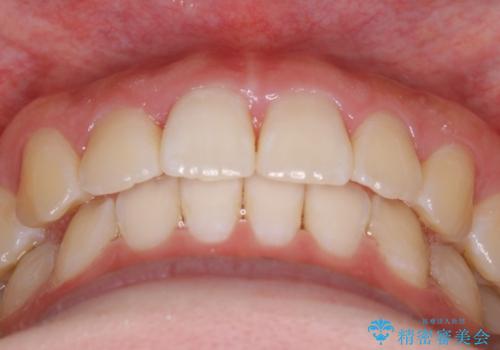

精密検査の結果奥歯の噛み合わせのズレからくる前歯のガタつきであることが分かり、患者様と相談した結果、全体をしっかりと治療することをご選択なさったので奥歯から動かして噛み合わせと見た目の両方を治す治療プランとなりました。

下顎の歯は幸いガタつきが少なかったため、下顎を基準とし構成する方針としました。

初診時の写真では一見噛み合わせには問題がないように見えても、実際に精密な検査を行うと改善すべき点が見つかる場合も多くあります。

当院では、矯正治療は見た目の改善が主目的ではなく機能面を改善し自然に長持ちする口腔内環境を整えることに重きを置く必要があると考えます。